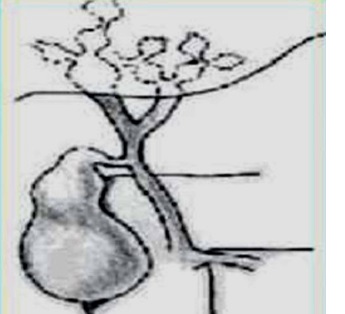

abdominale . Classification de Todani resume de cinq type de kyste choledoque

Type I est le

plus souvent a incidenece de 80-90% de

kyste du choledoque . Trois sous type Ia ,

Ib , Ic :

- Ia : Dilatation global

du canal choledoque

- Ib : Dilatation

segmentaire de VBP

- Ic : Dilatation

de voie biliare principale

Type II est diverticule de

VBP |

|

Type III dilatation

VBP a distal ( choledococele )

Type IV Dilatation du canal biliaire

extra et intra hepatique

Type V Dilatation de

voie biliaire intrahepatique ( maladie de

Caroli ) |